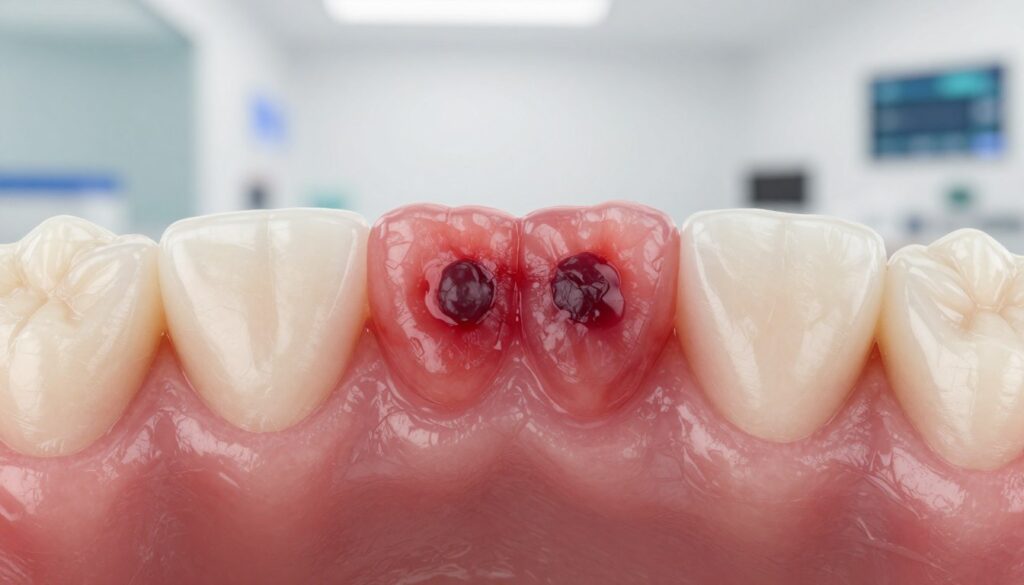

Jak wygląda krwiak w jamie ustnej i na dziąśle

Kolor i faktura zmiany pomagają odróżnić zwykły uraz od innej dolegliwości.

Typowa plama ma barwę od czerwonej, przez sinawą, aż po niemal czarną. Z czasem powinna blednąć i zmienić odcień.

Wyróżniamy dwie postaci: płaską plamkę oraz wypukły pęcherzyk wypełniony krwią. Pęcherzyk może delikatnie wystawać ponad powierzchnię błony śluzowej.

Najczęściej zmiany pojawiają się na dziąśle, policzku, wardze, języku lub podniebieniu. Niektóre miejsca, np. okolice podniebienia, bywają trudniejsze do samodzielnej kontroli.

Odczucia bywają różne: ból i tkliwość pojawiają się częściej po urazu, ale zmiana może też być bezobjawowa.